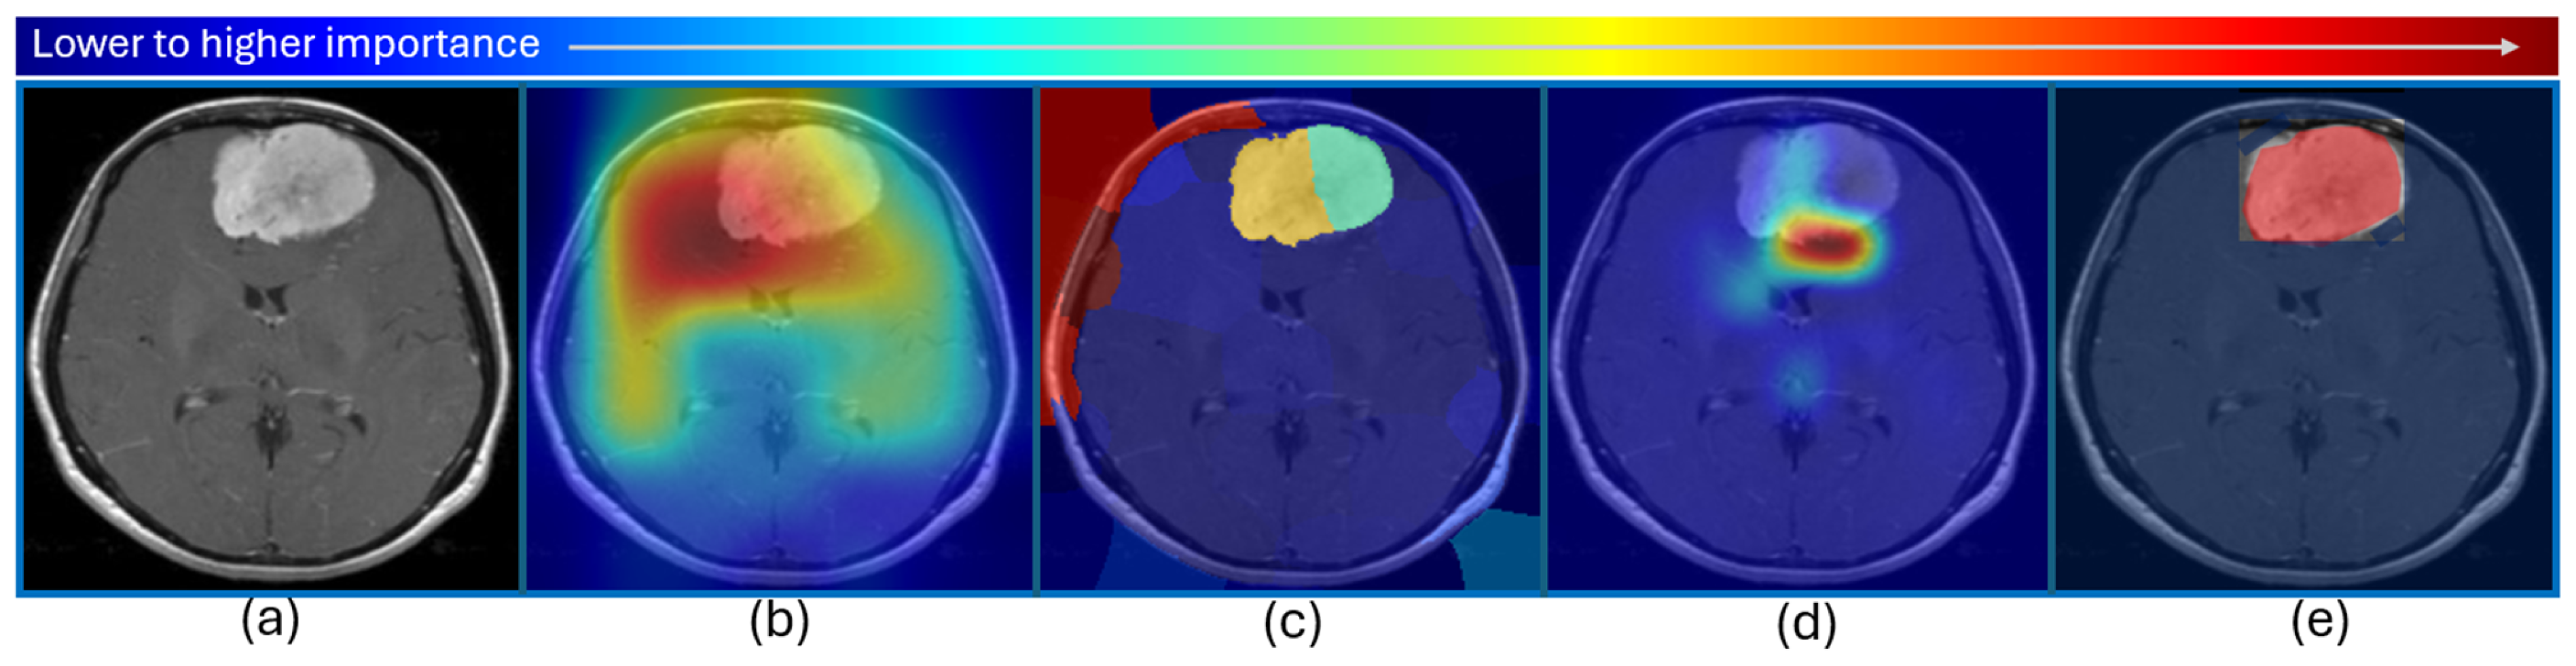

| [12] 2022 | Brain tumor (classification and segmentation) | MRI | ResNet50 for classification, encoder–decoder neural network for segmentation | - | Vanilla gradient, guided backpropagation, integrated gradients, guided integrated gradients, SmoothGrad, Grad-CAM, and guided Grad-CAM visualizations | BraTS challenges 2019 (259 cases of HGG and 76 cases of LGG) and 2021 (1251 MRI images with ground truth annotations) |